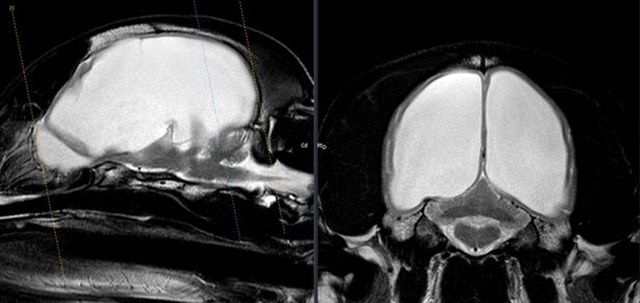

Gus’ blindness was caused by pressure growing inside his brain, according to scan results.

She said: “Gus had MRI and CT scans and Alexandra was amazed. She said he had the biggest case of hydrocephalus (fluid on the brain) that she’d ever seen and it was swamping both sides of his brain.